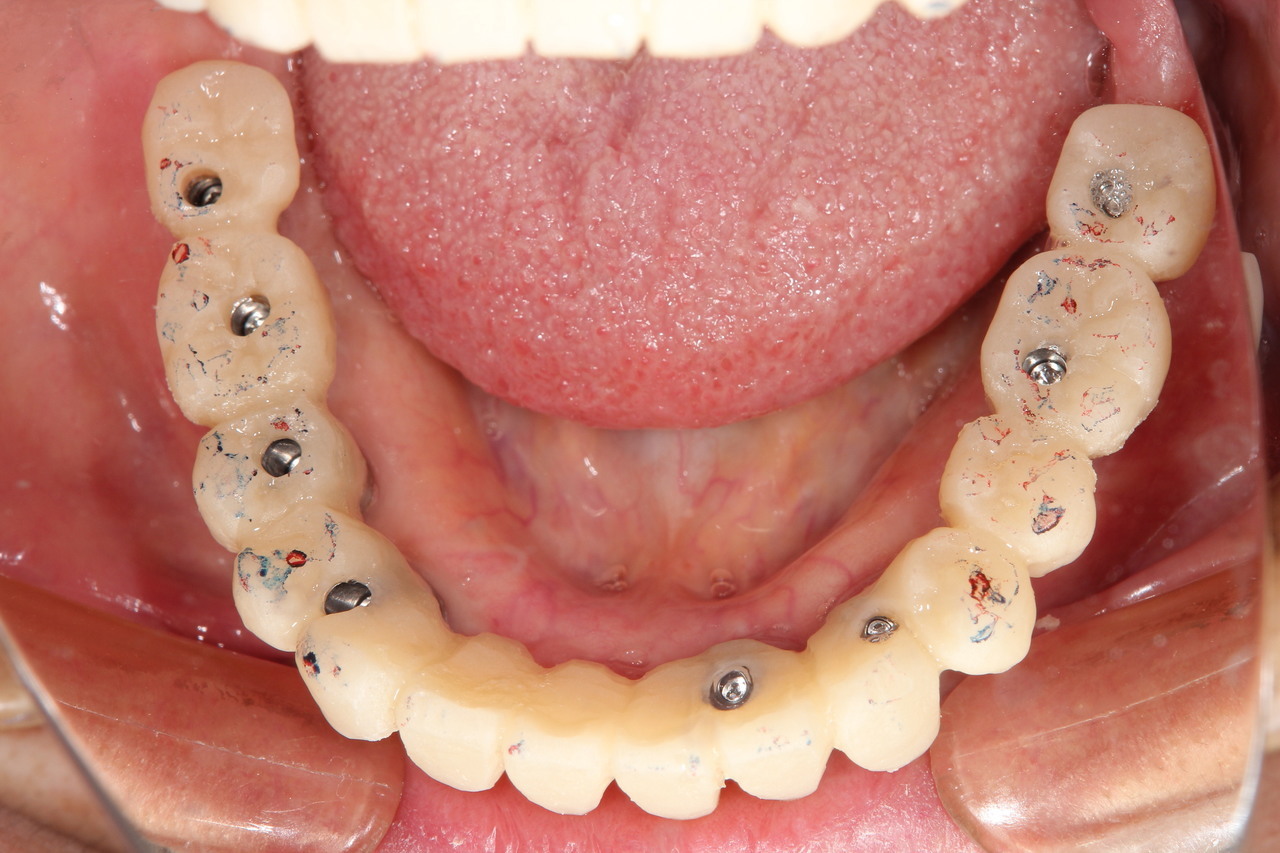

仮歯装着①

インプラント埋入後、その日に用意していた仮歯を装着します。

仮歯装着②

仮歯をネジ止めして固定します。

これはまだネジ穴を塞いでいない状態です。